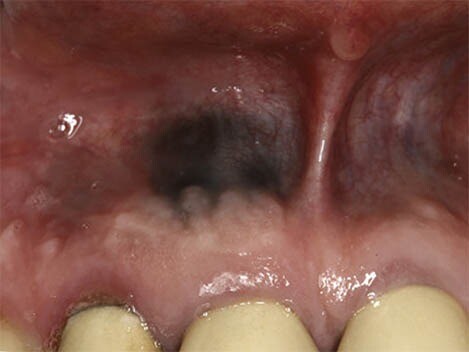

Oral Cancer

In rare cases, benign lesions that don't require treatment may transform into oral malignant melanoma, a type of oral cancer. A doctor will look at a range of factors to see if the lesion qualifies as melanoma. According to a research article published in the Journal of Indian Academy of Oral Medicine and Radiology, melanoma constitutes only 3–5% of all cutaneous malignancies, and oral melanoma is an aggressive neoplasm which accounts for less than 0.5%.

If you believe you have oral cancer symptoms, we recommend leaving the diagnosis up to the professionals and speaking to your doctor. If you exhibit symptoms, they may perform a biopsy (laboratory tests of your tissue) to confirm melanoma.

Remember that cancer is a rare cause of any dark spots in your mouth. A more benign explanation is much more likely, so don't stress. You've done a great job informing yourself of the possible causes, so be sure to make the next step for success and schedule an appointment or regular check-ups with your doctor.